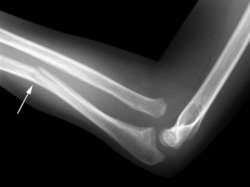

Golfers elbow or medial epicondylitis is an overuse injury similar to tennis elbow (on the outside of the arm) but causing pain on the inside of the elbow instead. It is sometimes known as throwers elbow or little league elbow. We explain the symptoms, causes and treatment to return you back to full fitness in the shortest time.